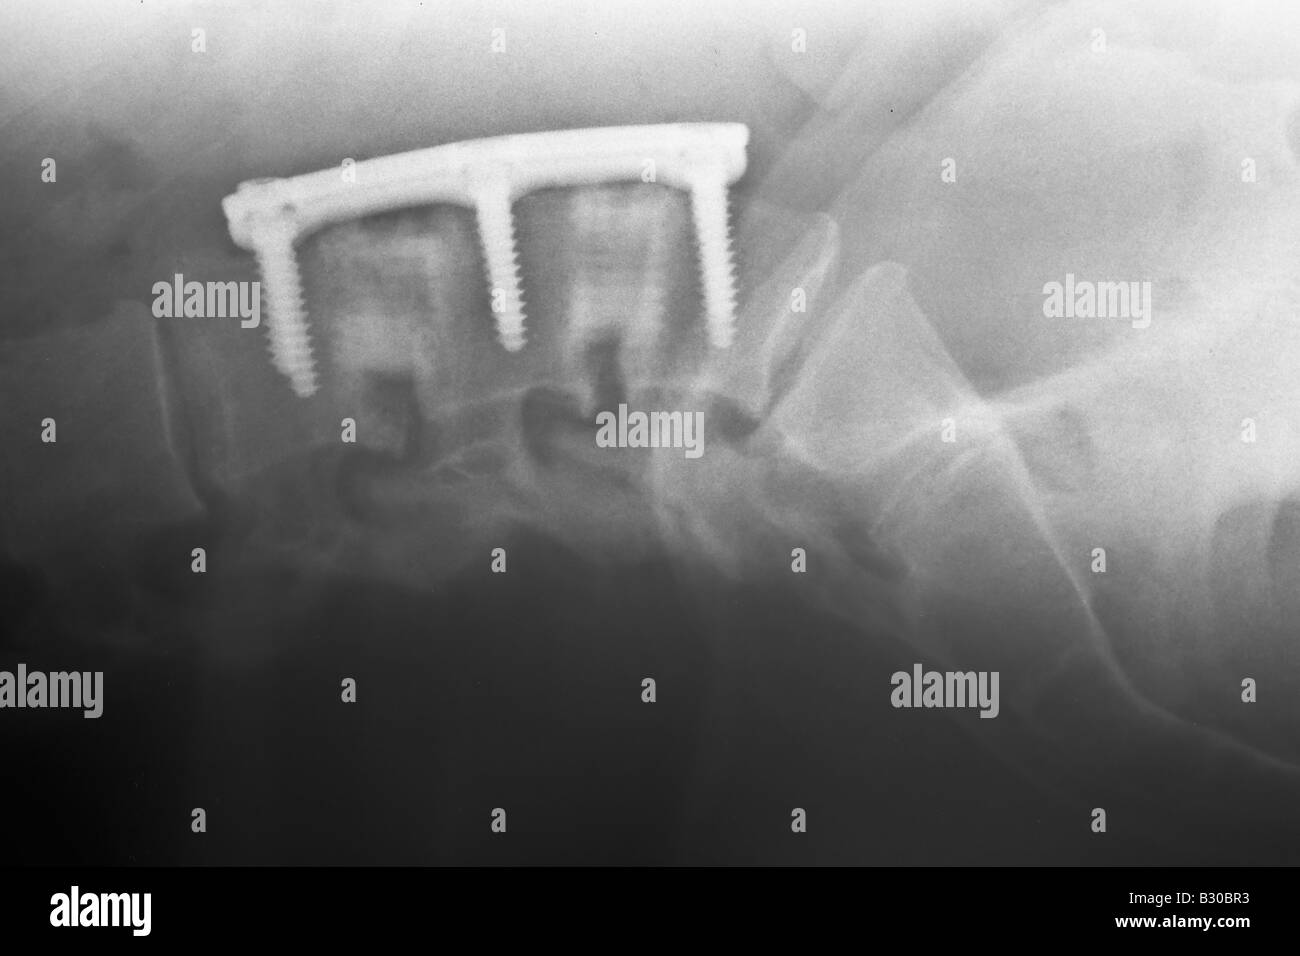

X ray of human lumber spine showing hardware used in an Anterior lumbar Hardware Failure Of Anterior Column Of Spine  Reported complications include thigh paresthesia from injury of the anterior cutaneous branch of the femoral nerve , ureter injury, pseudohernia of the abdominal. In an effort to gain an increased understanding of the need for revision surgery, the complications, and quality of life impairment associated with hardware failure, we. The earliest time to hardware failure was 1.1 months, and the. Hardware Failure Of Anterior Column Of Spine.

X ray of human lumber spine showing hardware used in an Anterior lumbar Hardware Failure Of Anterior Column Of Spine  The absence of anterior column reconstruction could result theoretically in a high incidence of hardware failure from compression fractures. Reported complications include thigh paresthesia from injury of the anterior cutaneous branch of the femoral nerve , ureter injury, pseudohernia of the abdominal. Anterior hardware impinging on anterior structures must be approached anteriorly. Patients were stratified according to the presence of. Hardware Failure Of Anterior Column Of Spine.

X ray of human lumber spine showing hardware used in an Anterior lumbar Hardware Failure Of Anterior Column Of Spine  Patients were stratified according to the presence of hardware failure. Failed posterior hardware may be approached. Anterior hardware impinging on anterior structures must be approached anteriorly. In an effort to gain an increased understanding of the need for revision surgery, the complications, and quality of life impairment associated with hardware failure, we. The earliest time to hardware failure was 1.1. Hardware Failure Of Anterior Column Of Spine.